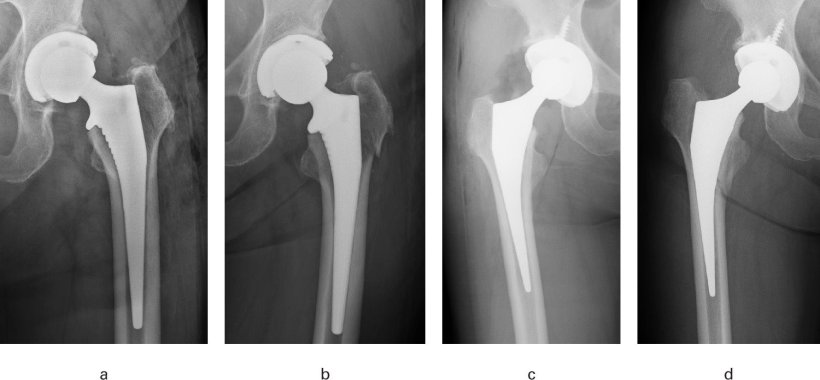

The two types of femoral stems compared were collared fully hydroxyapatite (HA)-coated stems and flat-tapered wedge stems. The first type features a stabilizing ring or ‘collar’ at the top of the implant that rests on the patient’s bone, and a specialized coating called HA, designed to promote bone growth directly onto the implant for a secure fit. Meanwhile, flat-tapered stems rely purely on their wedge shape and tight fit within the bone canal of the femur to achieve initial stability; they do not have a stabilizing collar or HA coating. “Based on both our clinical impressions and reports in the literature indicating a lower incidence of post-THR femoral fractures with collared fully HA-coated stems, we were inspired to investigate whether these stems could indeed reduce the risk of these fractures,” explains Dr. Hirasawa.

Image source: Hirasawa R, Oinuma K, Hagiwara S et al., The Bone & Joint Journal 2025 (CC BY 4.0)